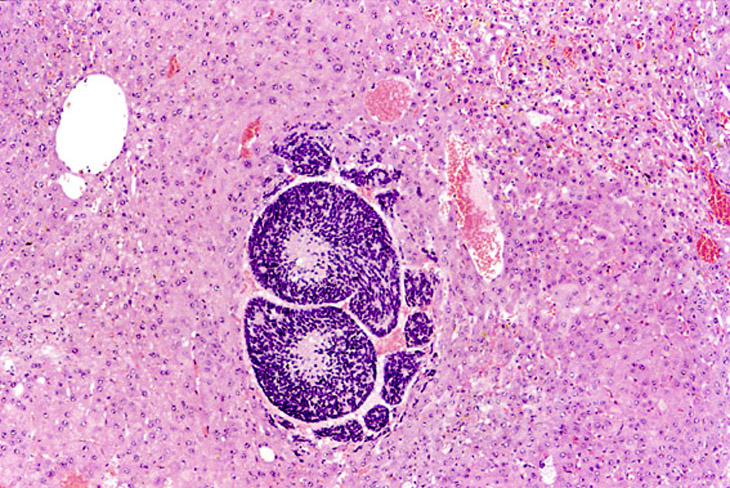

This small hepatoblastoma is present within an hepatocellular carcinoma.